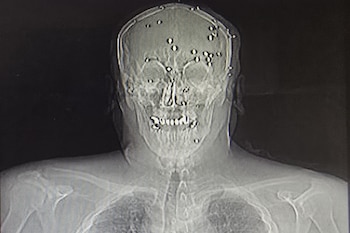

En la mañana del 9 de enero, el cirujano contactó a médicos de su confianza para derivarles pacientes. Primero, debía asegurarse de retirarles todas las balas y perdigones para que no fueran retenidos en el hospital. Escribió cartas de derivación indicando que los pacientes habían sufrido accidentes de tráfico.